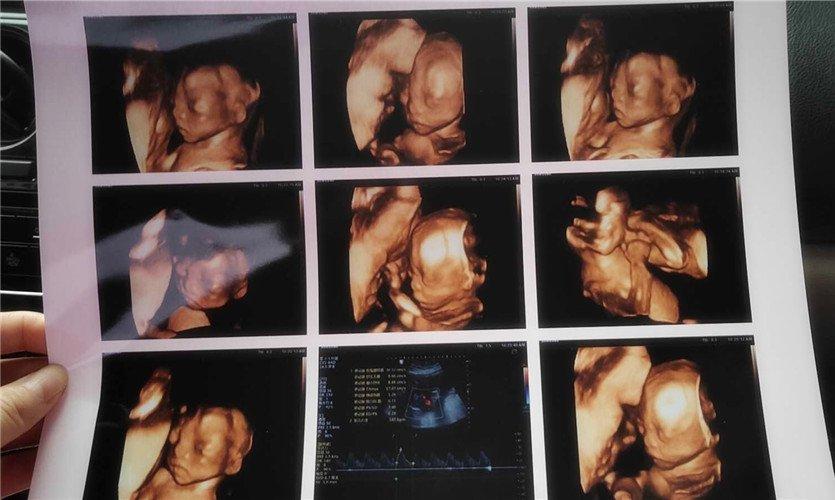

四維彩超是一種先進的醫(yī)學影像技術(shù),通過實時觀察胎兒在母體內(nèi)的活動情況,為醫(yī)生提供了豐富的診斷信息,在四維彩超下,我們可以清晰地觀察到胎兒的蛋蛋(睪丸)的形態(tài)、位置和大小等特征,胎兒蛋蛋是男性生殖系統(tǒng)的重要組成部分,對于胎兒的生長發(fā)育具有重要意義。

在四維彩超下,胎兒蛋蛋呈現(xiàn)出特定的形態(tài)和外觀,通常情況下,胎兒蛋蛋呈現(xiàn)出圓形或橢圓形,表面光滑,內(nèi)部回聲均勻,隨著胎兒的發(fā)育,蛋蛋會逐漸增大,并呈現(xiàn)出明顯的性別特征,醫(yī)生可以通過四維彩超技術(shù),對胎兒蛋蛋的大小、形態(tài)和位置進行評估,以判斷胎兒生殖系統(tǒng)的健康狀況。

胎兒蛋蛋的發(fā)育是一個復(fù)雜的過程,受到多種因素的影響,在胎兒發(fā)育的早期階段,蛋蛋位于腹腔內(nèi),隨著胎兒的生長發(fā)育,蛋蛋逐漸下降至陰囊,這個過程受到激素、遺傳和環(huán)境等多種因素的影響,在四維彩超的觀測下,我們可以實時了解胎兒蛋蛋的發(fā)育過程,及時發(fā)現(xiàn)異常情況并采取相應(yīng)的治療措施。

四維彩超技術(shù)在評估胎兒蛋蛋發(fā)育方面具有重要意義,通過四維彩超,醫(yī)生可以實時觀察胎兒蛋蛋的形態(tài)、位置和大小等特征,了解胎兒生殖系統(tǒng)的發(fā)育情況,四維彩超還可以幫助醫(yī)生發(fā)現(xiàn)可能的異常情況,如睪丸未降、睪丸囊腫等,為及時采取治療措施提供依據(jù)。